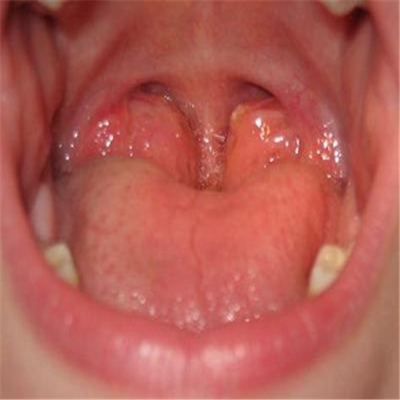

扁桃體惡性腫瘤圖片

扁桃體癌圖 (69)